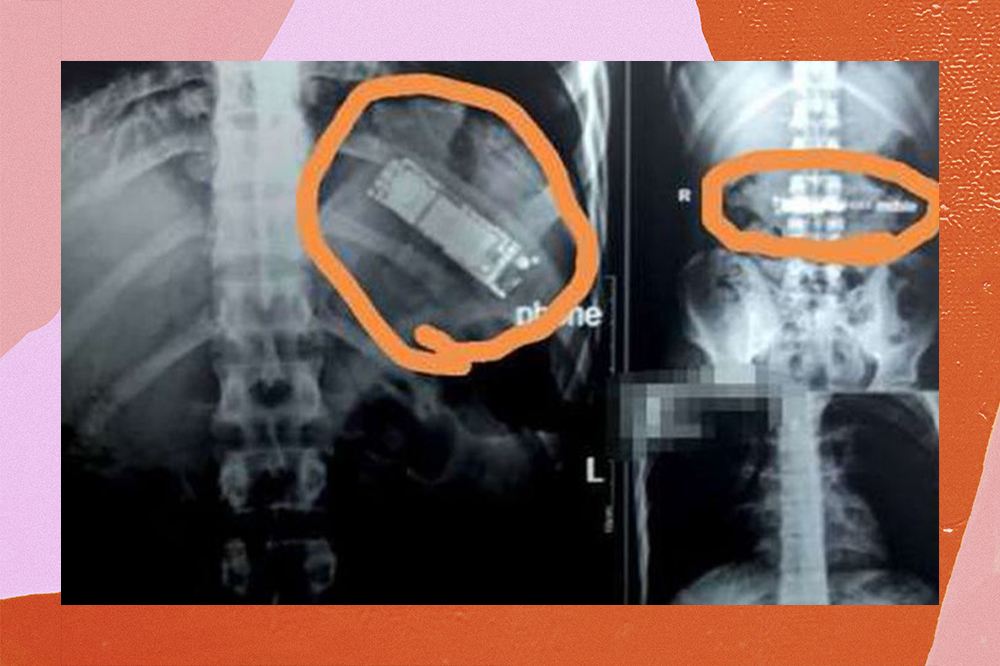

Homem engole celular “de zoeira” e passa sete meses com ele no estômago

O cara de 28 anos foi desafiado pelos amigos e achou que conseguiria regurgitar o aparelho sem maiores problemas